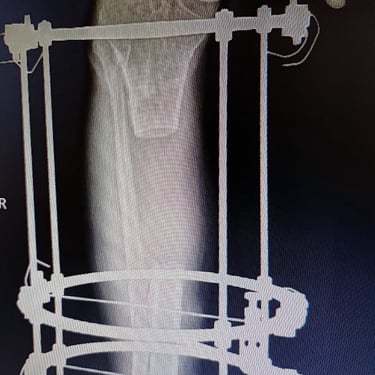

Gallery